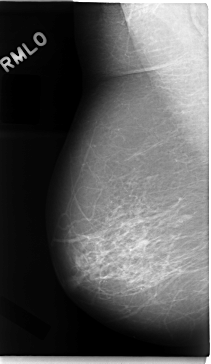

C_0018_1.RIGHT_MLO

RIGHT_MLO LINES 4720 PIXELS_PER_LINE 2736 BITS_PER_PIXEL 12 RESOLUTION 50 NON_OVERLAY